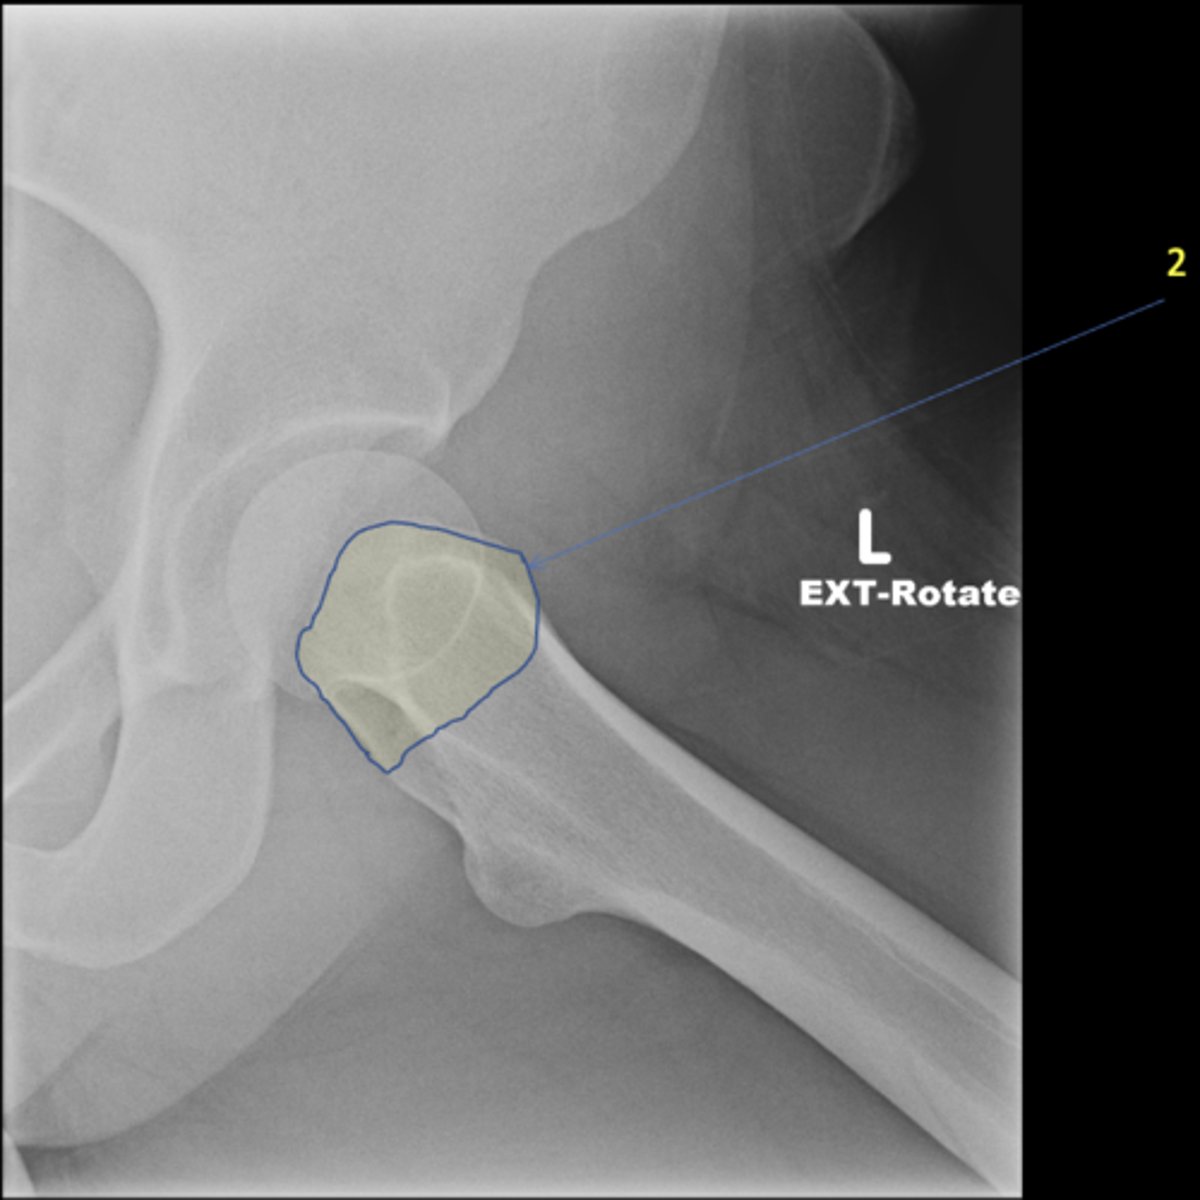

2

New cards

Right lesser trochanter

ID 2

<p>ID 2</p>